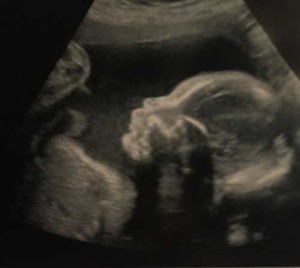

Eager to Meet Baby Boy Tate!

We are eager to meet our sweet baby boy, Tate, who is scheduled to make his debut in just 8 weeks!